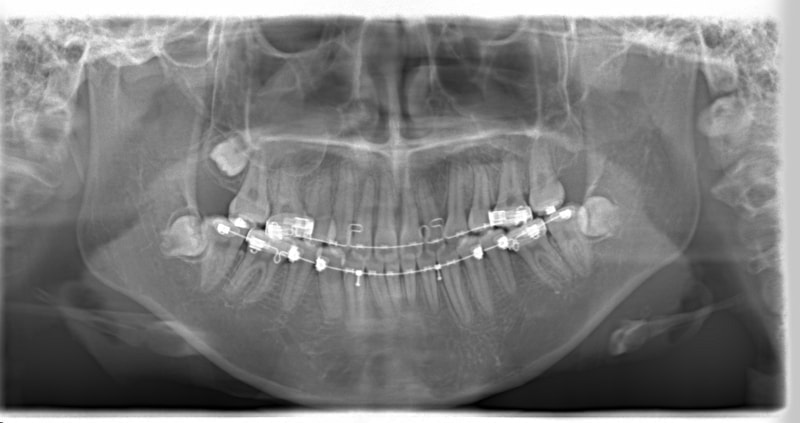

治療開始から11ヶ月後